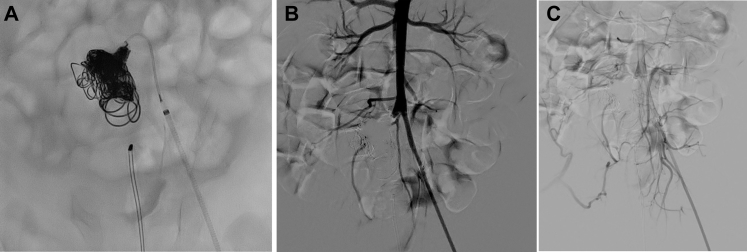

Fig 3.

A, Deployment of the last coil. B and C, Final digital subtraction angiography showing complete exclusion of the aneurysm (B) with prevention of the blood supply to the lower right extremity (C).